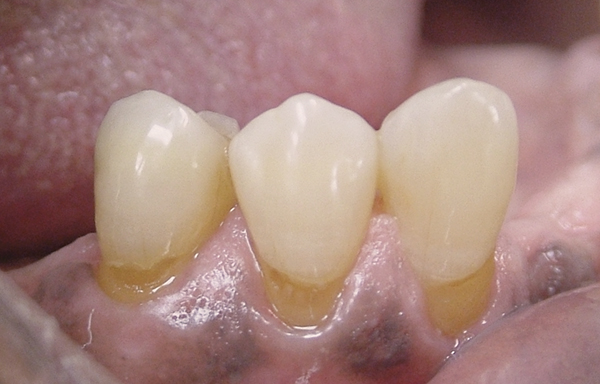

(Figure 3.) Gingival recession with exposed root surfaces are susceptible to dentinal hypersensitivity non-carious cervical lesions on the facial surfaces of mandibular teeth with symptoms of dentin hypersensitivity and in need of restorations

Figure 3